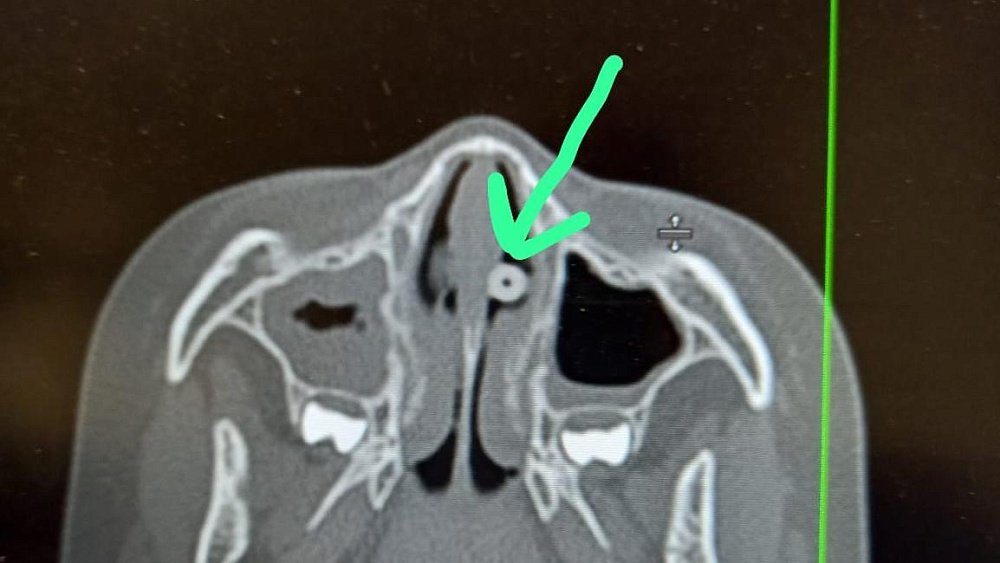

«Ребенок был направлен на компьютерную томографию по поводу болей в голове. Во время обследования в среднем носовом ходу обнаружили инородное тело, которое в дальнейшем наш врач-оториноларинголог Игорь Кузьмин успешно удалил с помощью эндоскопической техники. Это оказалась бусинка», — рассказала заведующая диагностической службой ЦОМиД Магнитогорска Юлия Терехова.